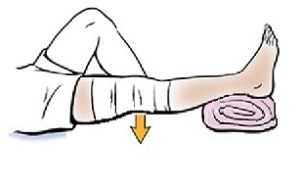

یکی از سادهترین و مؤثرترین تمرینها برای تقویت این عضله، حرکت بالا نگهداشتن پای صاف در حالت خوابیده است که به آن Straight Leg Raising (SLR) گفته میشود.

نحوه انجام تمرین : حتما با همراه داشتن ساعت انجام شود

- روی زمین یا تخت در حالت خوابیده به پشت قرار بگیرید.

- یکی از پاها را کاملاً صاف نگه دارید و زانو کاملا صاف باشد .

- پنجه پا را به سمت صورت بکشید تا عضلات پشت ساق پا نیز کشیده شوند.

- با انقباض عضله چهارسر، پای صاف را از زمین بلند کنید تا پاشنه حدود ۲۰ تا ۳۰ سانتیمتر از سطح زمین فاصله بگیرد.

- پا را در همین حالت به مدت ۱۰ تا ۲۰ ثانیه نگه دارید (بر اساس توانایی شما).

- سپس پا را بهآرامی پایین بیاورید و همین حرکت را با پای دیگر تکرار کنید.

– این تمرین را در طول روز حداقل دو سری 5 باره انجام دهید.

– هر زمان که توانستید بهراحتی پا را برای مدت تعیینشده بالا نگه دارید، زمان نگهداشتن را افزایش دهید (مثلاً از ۲۰ ثانیه به ۳۰ ثانیه).

– هدف نهایی این است که بتوانید پا را با زانوی کاملاً صاف، بدون لرزش و بدون درد، به مدت ۶۰ ثانیه بالا نگه دارید.

این تمرین ساده، بدون نیاز به تجهیزات خاص، میتواند تأثیر بسیار زیادی در آمادگی شما برای جراحی و بهبود سریعتر پس از آن داشته باشد.

نحوه قرار دادن اندام تحتانی پس از عمل :

پس از جراحی، نحوه قرار دادن پا بسیار مهم است. باید بالش زیر ساق پا و مچ پا قرار گیرد، نه زیر زانو. زیر زانو باید خالی باشد تا پا کاملاً صاف قرار گیرد. بیمار باید با انقباض عضله چهارسر تلاش کند زانو را به سمت پایین فشار دهد تا فضای خالی زیر زانو پر شود و زانو صاف شود.